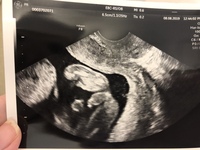

妊娠 18w-妊娠18w0d おなまえ もやしちゃん ねんれい 妊娠週 22w5d 18wの時のエコー写真です。 一応女の子ぽいねと言われました! 18wからもう胎動を感じ 病院でも落ち着きがないと 言われる元気な子です\ (^o^)/ 可愛くていとおしくて 早く逢いたいです。 明日は検診なので 顔がもっとしっかり見れたら いいなと思ってます。 おなまえ もこのじSep 09, 17 · 妊娠糖尿病宅食サービス徹底比較!味は?サービスは?勝手にランキング♡口コミ 私が妊娠糖尿病と診断されたのは18w(妊娠中期)の時。 自覚症状も全くなく、突然の診断にただただビックリ。

Mar 17, 05 · 現在妊娠18週で、初産です。 胎動のことでお伺いします。 昨日初めて、お腹の中でポコポコッていうような感覚がありました。 胎動を感じるのをずっと楽しみにしていたので、本当にこれかなあ? と思いながらも、とても嬉しいです。 ところで、こういう感覚って、どのくらい頻繁に感じるものなのでしょうか? はじめのうちは1日に何度も感じるものではないAug 24, · 妊娠後期の"苦しい"タイミング別にケア法などをまとめます。 「座っていても苦しい」ときは? 生活の中で頻繁に行う「座る」という動作。妊娠後期になると、この状態で苦しくなることも少なくありませんが、その場合の原因は複数考えられます。妊娠週 18w0d 1ヵ月ぶりのエコーは、大きくなっていて画面に入らなくなっていて、驚きました♪週数通りの250g程みたいです。 足をしっかり挙げてVの字になっていて笑ってしまいました。 先生には「性別は次の検診の時かなぁ」って言われたけど、エコーの股の間には丸いものが見えたので、もしかして男の子かなぁと夫婦で推察しています。 おなまえ 楓 ねん